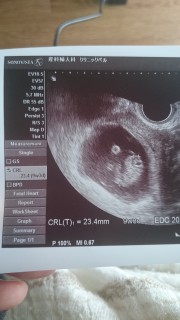

CRL2.77cmでした。だいたい平均くらいかと思います。 5w5dのときには人の形には見えなかったのですが、今回の診察で2頭身になり、手足も見えるようになりました。とても可愛らしく思います。 関係ありませんが、担当の先生がいつもと違う方で、結構ぐりぐりやられたので地味に痛かったです…。

初めから排卵がズレてたので9w3dに(^^) 大きさは2.4cmぐらい♡ エコー中は寝てたみたいで動かず^^; でも手足がもうちゃんと分かるー♡ 予定日がパパとお兄ちゃんの誕生日の3日後♪ 赤ちゃんも一緒の誕生日になったら奇跡だな~♡ 次の検診は3週間後! すくすく赤ちゃんのペースで育ってね♪